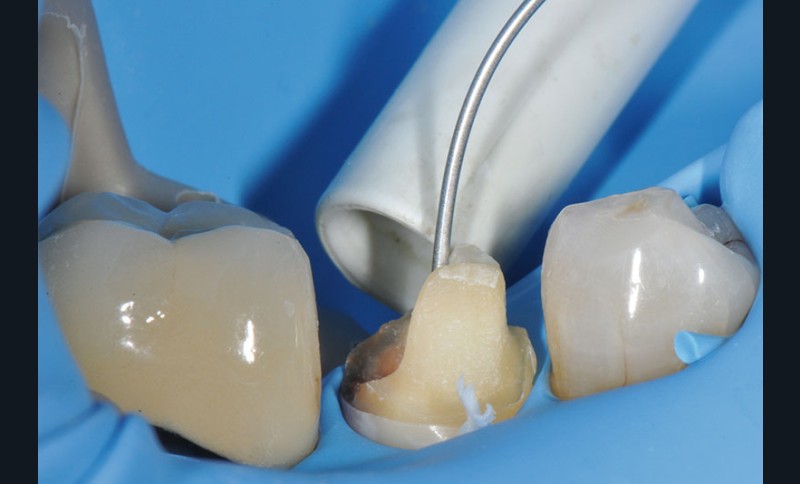

7, 8, 9. L’obturation canalaire à la gutta percha est partiellement éliminée avec le foret universel et le canal radiculaire est mis en forme avec le foret de calibrage 3M™ RelyX™ Fiber Post de 1,1 mm de diamètre. L’élimination totale de la gutta percha sur la longueur désirée est vérifiée à l’aide d’une radiographie rétro-alvéolaire. Un insert à ultrason est utilisé, son action mécanique permettant de finir de nettoyer le système canalaire et d’éliminer les résidus de ciment endodontique pouvant encore être présents.